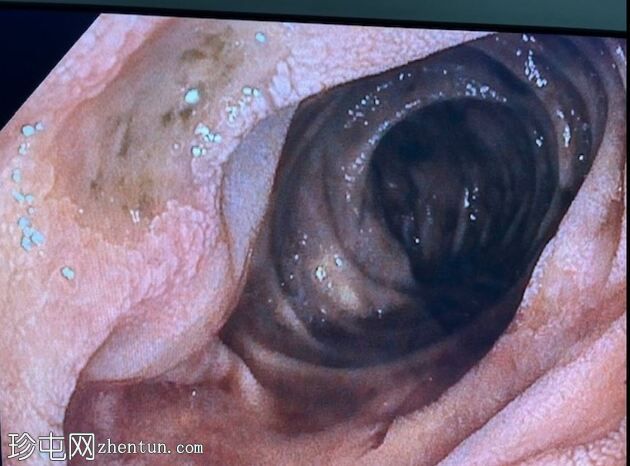

胃底可见变质血液

内镜报告:

食管:LA C级食管炎。

胃:胃底可见变质血液及大血块。吸痰、冲洗并调整患者体位以移动血块后,未在胃底或胃体部发现病变。未发现活动性出血点。